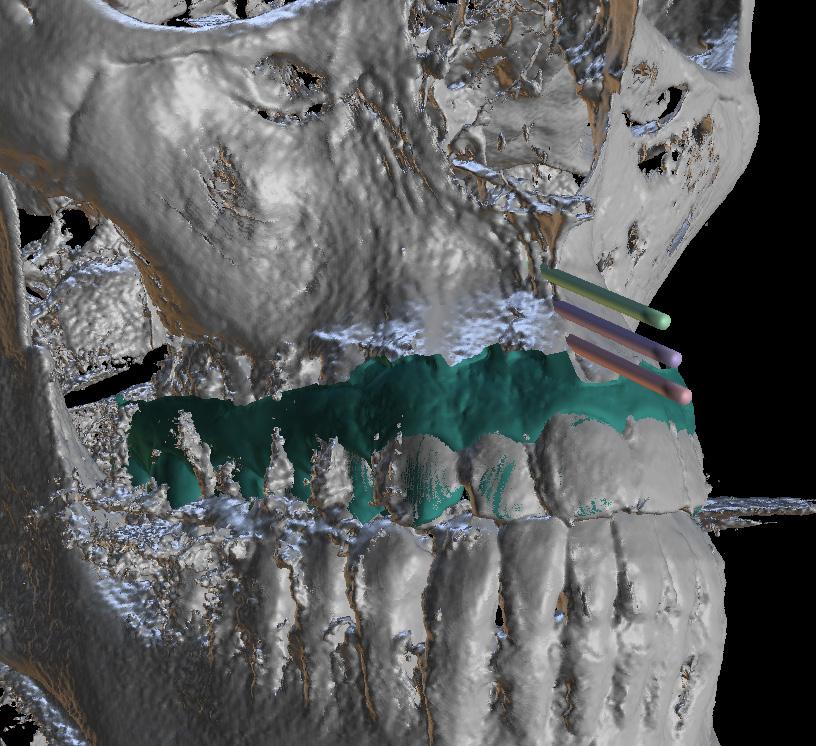

Standard orthodontic pretreatment records (T0) were obtained (Figure 1). The same operator obtained the lateral cephalogram and OPG using the same machine. The lateral cephalograms were traced manually with the standard technique by a single

investigator and a total of 06 skeletal, 11 dental, and 03 soft tissue parameters were measured. Selected patients were also subjected to Acoustic pharyngometry (AP) for a three-dimensional evaluation of the upper airway. Fixed orthodontic appliance (022” MBT PEA) was bonded on both maxillary and mandibular arch, with banding of first & second molars. A standard wire sequence was followed till the full slot engagement with SS wire (19 X 25”) was achieved. A complete set of records were made to register the beginning of the fixed functional phase (T1) (Figure 2). Forsus appliance (FFRD) was fitted for each patient, push rod hooked on the archwire between canine and 1st premolar in the maxillary arch and distal end of open coil spring connected with the ‘L’ pin to the 1st mandibular molar. Maxillary and mandibular components of the Forsus FRD were connected to provide a forward thrush to the maxilla and a backward thrust to the mandible during the closure of the mouth (Figure 3). The functional phase with Forsus FRD continued till the desired objectives were achieved i.e., achieving positive overjet as well as satisfactory improvement in soft tissue profile.

To enhance the skeletal effects of the Forsus appliance, the indirect anchorage was obtained using TADs (temporary anchorage devices), placed in the maxillary arch, distal to canine. Post-functional records were made after the removal of Forsus FRD (T2) (Figure 4). Fixed orthodontic therapy continued to settle the occlusion and patients were debonded (Figure 5).